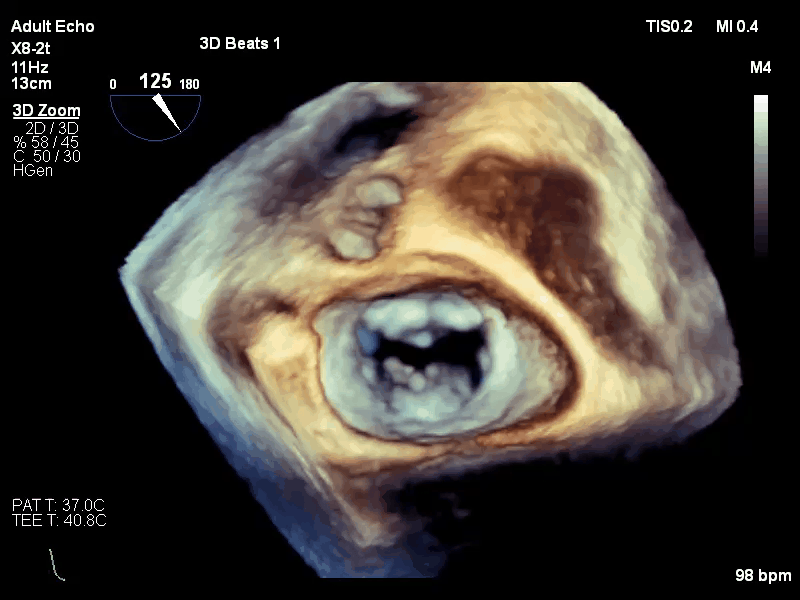

手术过程:

手术于全麻下进行,采用股静脉房间隔途径,房间隔穿刺后置入外径22F导管鞘及夹合器输送系统,在TEE引导下,将1枚长宽型号的KoKaClip®夹合器顺利植入到二尖瓣2偏1区,夹合器位置稳定。彩色多普勒超声未见明显残余反流,肺静脉多普勒波形由反向恢复正常。多切面证实夹合组织充分,双孔化形成,遂移除器械输送系统,移除后夹合器活动度小,手术顺利完成,患者已于近日出院,出院超声复查良好。

释放后

出院复查